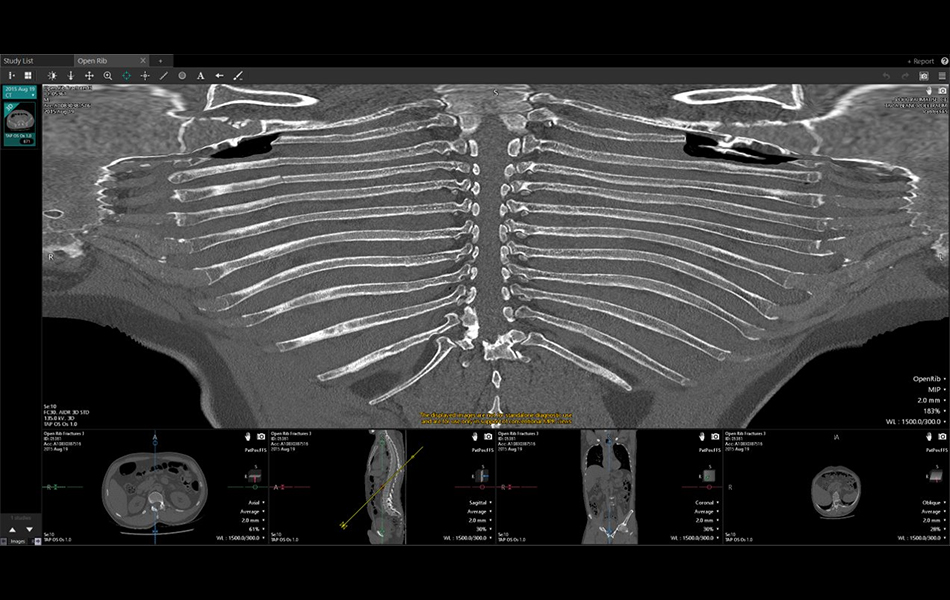

Open Rib (7.15.8)

The Open Rib application is image analysis software for chest CT images. The application offers a visualization of the unfolded rib cage that allows a physician to instantly view the full rib anatomy and should be used as an additional view in adjunct to conventional multiplanar reformat views.